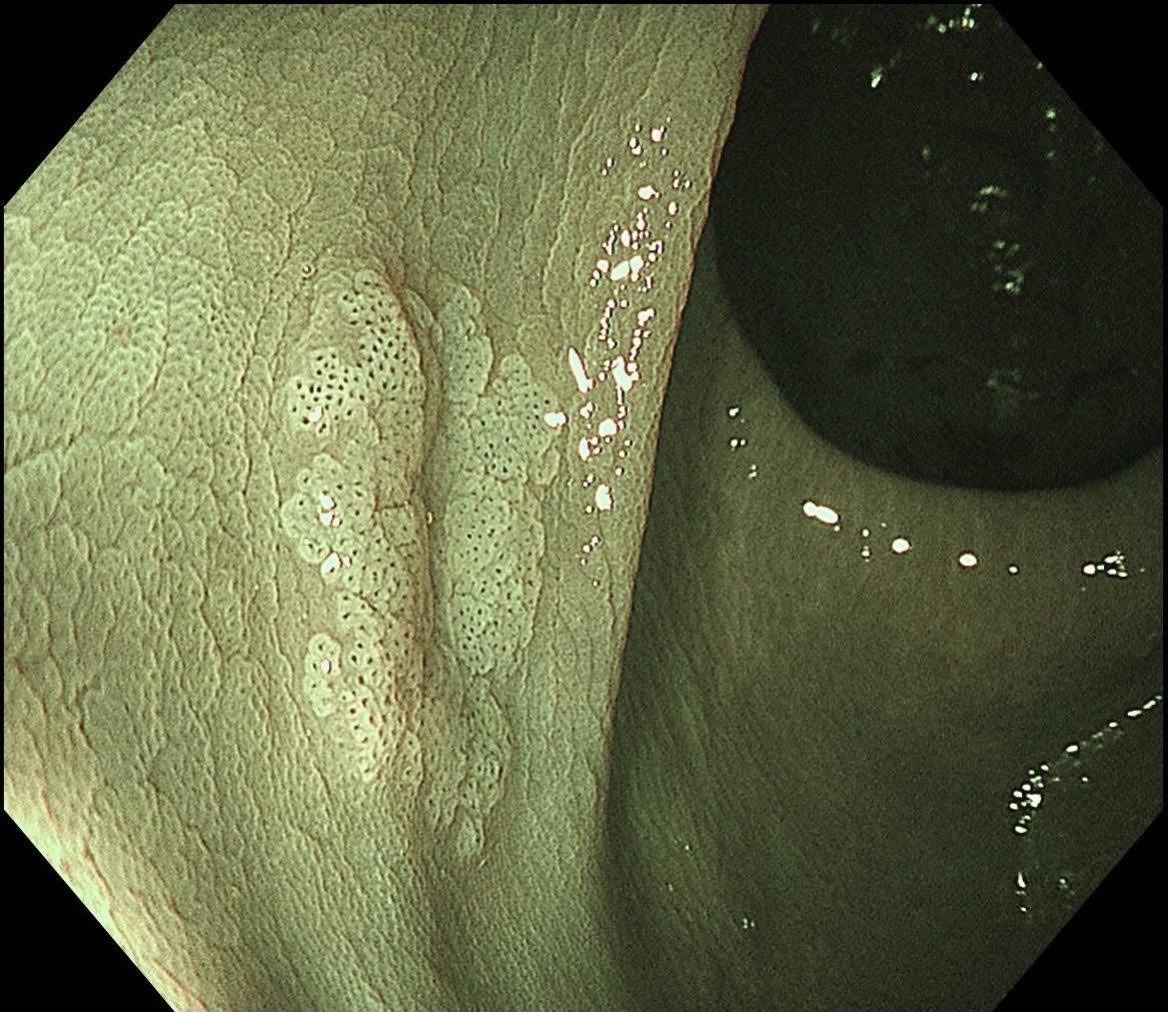

结肠SSL 醋酸染色。染色效果不亚于靛胭脂,结合NBI,Near focus观察表面结构非常OK,下次让护士长买大桶装的,1桶6块9,可以喷一年,哈哈……

结肠SSL 醋酸染色。染色效果不亚于靛胭脂,结合NBI,Near fo...